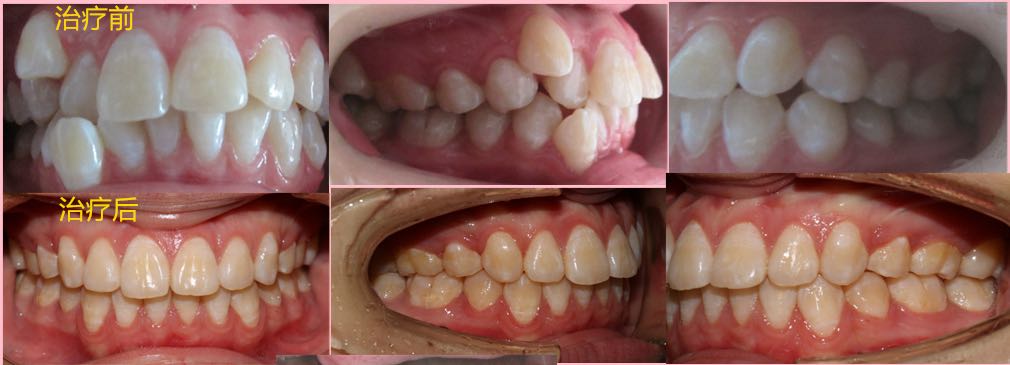

患者,女,14岁

患者神清气平,对答切题,生命体征平稳。面部基本对称,皮肤无红肿。口腔卫生良好,开口度及开口型正常,关节无弹响。双侧磨牙轻远中关系,右侧上颌尖牙位于牙弓之外,上颌重度拥挤,下颌中度拥挤,前牙深覆合I°,深覆盖II°,下颌中线居中与面中线一致,上颌中线右偏,面部左右不对称,右侧丰满,左侧欠丰满,上颌发育正常,下颌稍后缩,偏高角。

2、直丝弓拔牙矫治,拔牙部位为:14,24,34,44,上下颌中度支抗,排齐整平牙列,关闭拔牙间隙,调整中线及咬合关系。